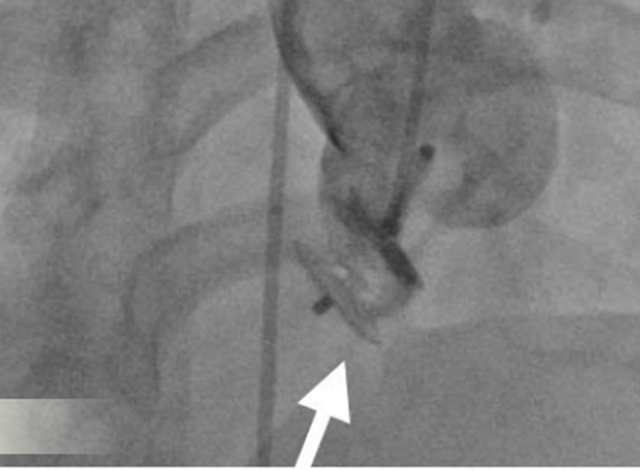

Bác sĩ can thiệp bít kín thành công bằng dù xoang Valsalva

Thông qua siêu âm tim qua thực quản, các bác sĩ đã xác định chính xác vị trí lỗ vỡ của xoang Valsalva, đo được kích thước của lỗ vỡ; cũng như đánh giá khoảng cách từ vị trí vỡ đến lá van động mạch chủ.

Những thông số này có ý nghĩa quyết định, không chỉ giúp đánh giá mức độ nguy hiểm của bệnh lý mà còn là cơ sở để lựa chọn phương pháp điều trị tối ưu, an toàn, tránh ảnh hưởng đến các cấu trúc tim quan trọng như van động mạch chủ và động mạch vành.